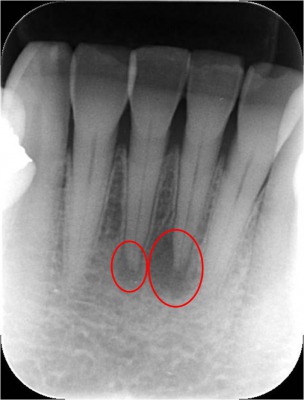

下顎前歯の痛みと歯茎の腫れを主訴に来院されたました。

レントゲン写真で確認すると根尖にレントゲン透過像が確認できます(右写真の赤色の丸の部分です)。

- 初診時